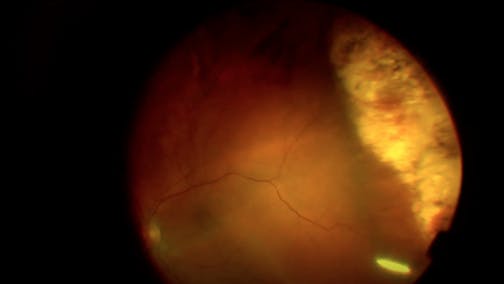

Optic Nerve Pit

Kourous A. Rezaei, MD